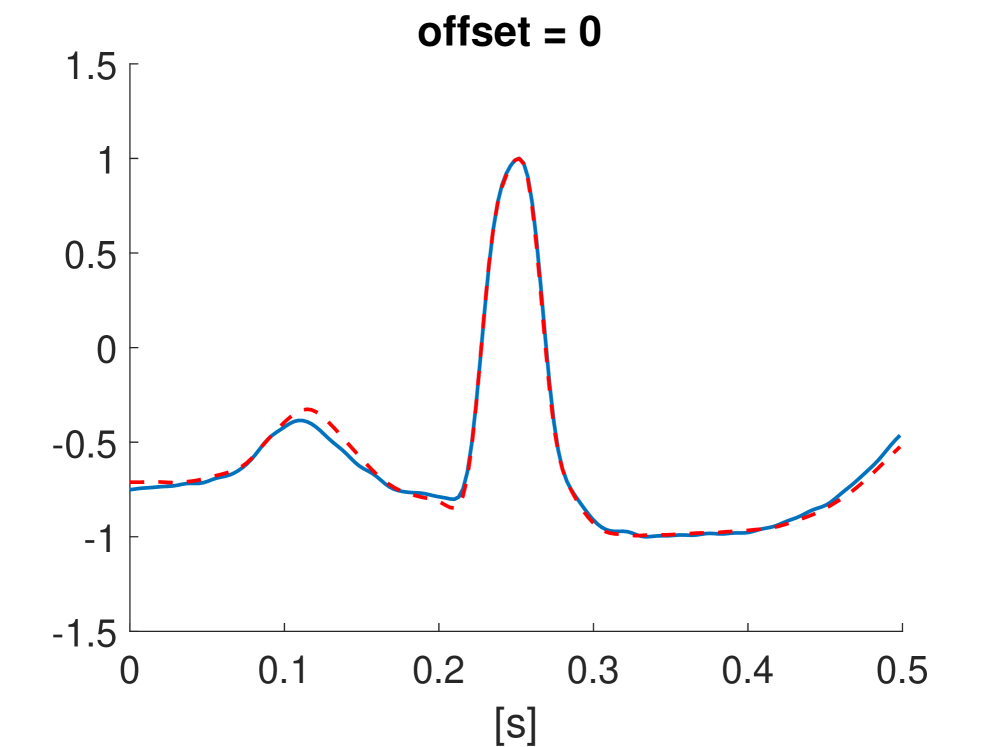

Fig. 10 shows the result in input space of moving along the first principal components in the latent feature space. As original base point we take a normal beat signal, i.e. corresponding to a hidden unit on the bottom right of Fig. 9(a). The smooth transition between the beat patterns allows for interpretation of the first principal components. This allows a clinical expert to understand on what basis the paced beats are separated by the principal components and if this basis has a physiological meaning. In order to investigate the separated region of the latent space at the top of Fig. 9(b) we start from a paced beat pattern and vary along the third principal component. This allows us to see which sort of heartbeat patterns are responsible for this specific distribution in the latent space.